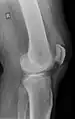

Quadriceps tendon rupture in plain X-ray